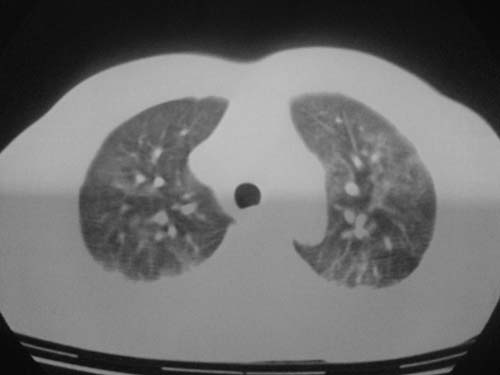

这是第三天拍的片子.